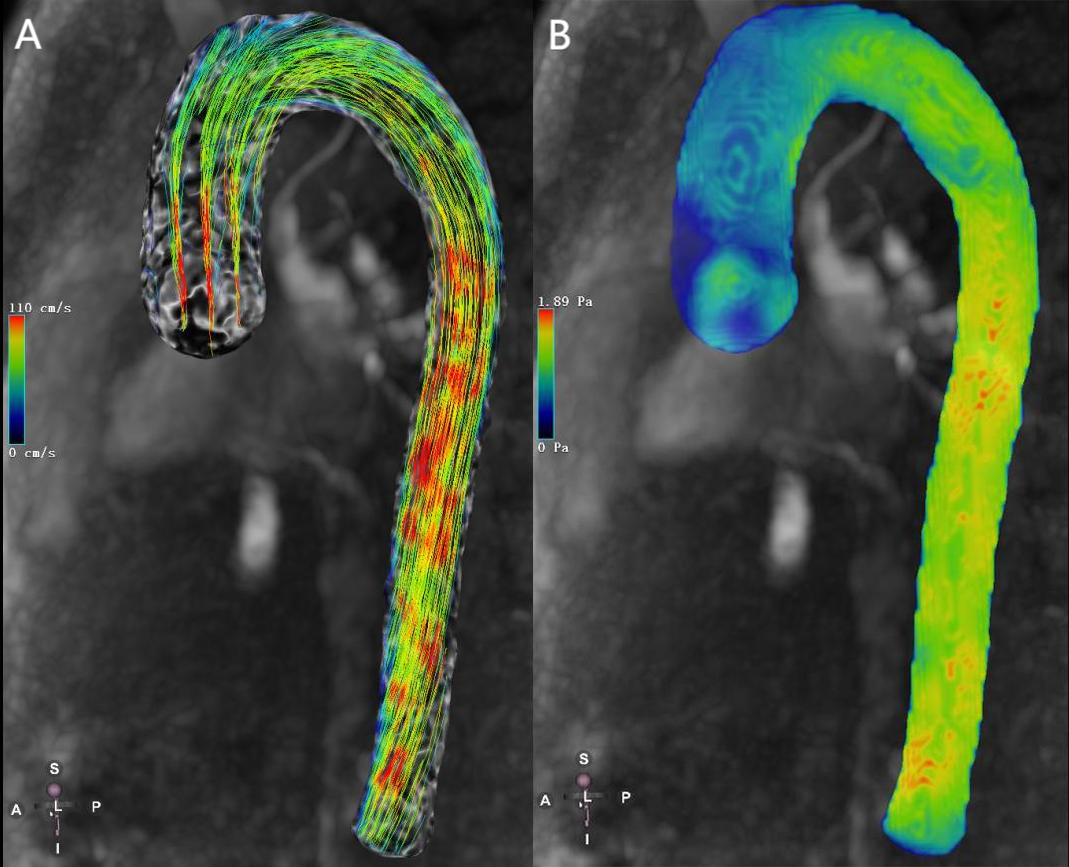

Efficient post-processing software is essential for the quantification and visualization of hemodynamic parameters in both scientific research and clinical applications. The example of 4D flow MRI–based visualization of aortic hemodynamics is shown in Fig. 1. Current post-processing software includes CAAS 5.1 (Pie Medical Imaging, Maastricht, Limburg, the Netherlands), CVI42 6.0.2 (Circle Cardiovascular Imaging, Calgary, Alberta, Canada), GT Flow 3.1.14 (GyroTools, Zurich, Switzerland), iT Flow 1.9 (Cardio Flow Design Inc., Chiyoda-ku, Tokyo, Japan) and MEVISFlow 10.3 (Fraunhofer MEVIS, Bremen, Germany). In addition, some researchers have developed advanced flow analysis parameters using MATLAB R2022b (MathWorks Inc., Natick, MA, USA) or other programming languages to visualize the advanced flow data using post-processing tools in the field of fluid dynamics, such as Ensight and Paraview. It is important to note that there are significant differences in WSS quantitative reference values derived from different post-processing software [16]. These discrepancies may be related to variations in background phase offset corrections, contour splitting, and software algorithms.

Fig. 1. 4D flow magnetic resonance imaging (MRI)–based visualization of aortic hemodynamics in a healthy volunteer. (A) 4D-flow-Image streamlines for the aorta. (B) 4D-flow-Image wall shear stress for the aorta. The color gradient change reflects the magnitude of velocity and wall shear stress (WSS). Red and blue are the maximum and minimum values, respectively. 4D, four dimensions.

Limitations: The lack of uniformity in WSS measurement limits its clinical application. However, it has been suggested that aortic remodeling can be predicted by differentiating between areas of high and low WSS [17]. In the future, standardization of scanning protocols and uniformity of post-processing methods are needed before 4D Flow can be introduced into routine clinical applications.